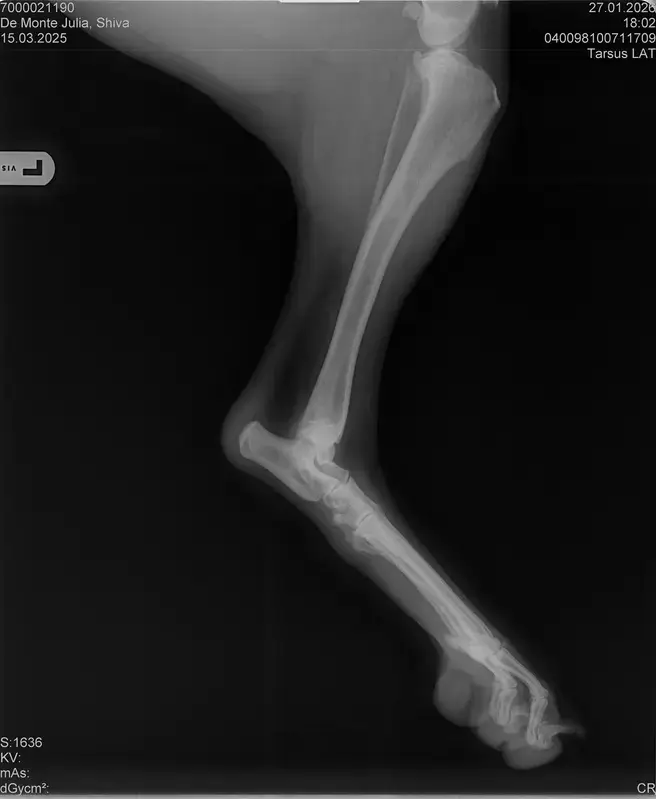

Vorige Woche kam mir Shiva verändert vor, nicht der aufgeweckte Spaßvogel der er sonst ist. Ich dacht vl ist er im Garten iwie blöd ausgerutscht weil unser gesamtes Grundstück über Wochen von einer dicken Eisschicht überzogen war. Er lag viel rum, zuviel da er doch zu den Wirbelwinden unter den Junghunden gehört. Er quetschte sich zum schlafen an mich ran, was auch untypisch für ihn ist. Er ist immer so „iiiii fass mich nicht an“. Ich nehms ihn nicht böse er ist nicht der große Kuschler :D Hat er wohl von mir :D :D aber er pickte nur an mir dran, ruhen ohne Körperkontakt war nicht möglich. Fand ich schön aber da ich wusste dass es nicht Shiva ist machte ich mir schon Sorgen… Am nächsten Tag wollte ich ihn bürsten alles war wie immer, er legte sich hin und sah mir zu wie ich einen Fellberg stapelte. Bei seinen Hinterpfoten hörte ich auf und dachte mir ich fühl mal vorsichtig.. Plötzlich knurrte er mich an vor Schreck weil ich damit überhaupt nicht gerechnet hatte zuckte ich reflexartig zurück (was lt Trainerin ein Fehler war)… Aber ich hab nicht mit einer derartigen Reaktion gerechnet, Shiva hatte schon 2 kleine Verletzungen die ich ohne Probleme verarzten konnte. Am nächsten Tag gings ab zum TA. Mit Maulkorb da ich nichts riskieren wollte. Nach der Untersuchung wo er auch mehrmals knurrte gings ab zum röntgen. Und das riss mir den Boden unter den Füßen weg. Dann die Aussage von der TA „ich weiß sie wollen einen gesunden jungen Hund aber das ist Shiva leider nicht“. Was jetzt? Er ist so ein aufgewecktes Kerlchen, absolute Lieblingsbeschäftigung ist Parcour. Er macht es so gern, ja auch UO und Suchspiele aber das leuchten in seinen Augen wenn wir Geräte machen :( (er macht noch keine schweren Geräte wie A Tafeln oder springen… Aber die seichten macht er mit absoluter Leidenschaft.. Ruhe halten über mehrere Monate… nur langsames gehen oder schnüffeln.. puh ich weiß nicht wie ich ihm verbieten soll zu rennen und zu toben… Vl habt ihr Tipps für mich. Im Anhang der Befund und ein paar Bilder vom kleinen Wirbelwind. <3

• Naja die Diagnose kommt von einem „Facharzt“, lt TA war ihrerseits alles i.O. Sie wollte noch sicher gehen und die Bilder zur weiteren Befundung einschicken und das kam dabei raus. Und der Therapievorschlag beläuft sich auf Ruhe, Ruhe und noch mehr Ruhe. Und einer Schmertherapie von Gabapentin 800mg 1/2 Tablette 2x tgl, Carprodyl 120mg 1 1/2 Tabletten 1x tgl und TamaCan CBD Tropfen 10-15 Tropfen 2x tgl. 1x in der Woche soll ich telefonisch Auskunft geben wie es Shiva geht. Das ganze mal für 14 Tage. Sie meinte noch sie hat viele Junghunde die ein Leben lang Schmerzmittel nehmem müssten. Die Röhrenknochenentzündung heilt in der Regel von selber der Rest gehört beobachtet… Ich weiß im Moment auch nocht so recht.. Er tut mir nur wahnsinnig leid mit sovielen Diagnosen und für mich war erstmal vorrangig ihn schmerzfrei zu bekommen. Das ist er inzwischen und versteht die Welt nicht mehr warum er nicht wie sonst spielen und arbeiten darf. Im Anhang noch Röntgenbilder falls sich jemand damit auskennt bzw Interesse hat..

• Ok, die Röntgenbilder sind aber auch extrem schlecht.

Panostitis ist idR sehr schmerzhaft, aber nicht unüblich und heilt in der Regel von alleine aus, wichtig dabei ist schonen und Entzündungshemmer zu geben, damit das nicht chronisch wird. Ich denke, dass die Akut bemerkbaren Schmerzen hauptsächlich davon kommen. Also da passt die Empfehlung deiner TÄ für's Erste auf jeden Fall.

Wenn dieser Panostitis-schub rum ist, würde ich dem Rest nochmal nachgehen. Man kann bei Dr. Tellhelm ( SV Gutachter) ein privatgutachten in Auftrag geben, das kostet um die 100€. Da kriegst du halt ne konkrete Einstufung und nicht "verdacht auf" und "könnte hiermit ODER damit in Verbindung stehen", etc.

Ich denke aber, dass du für ein Gutachten von Tellhelm nochmal neu röntgen lassen musst, ich finde, dass das Bild der Hüfte (HD und LÜW wird da beurteilt) und die Draufsicht auf die Ellenbogen (nötig zur Beurteilung von ED) unterirdisch sind!